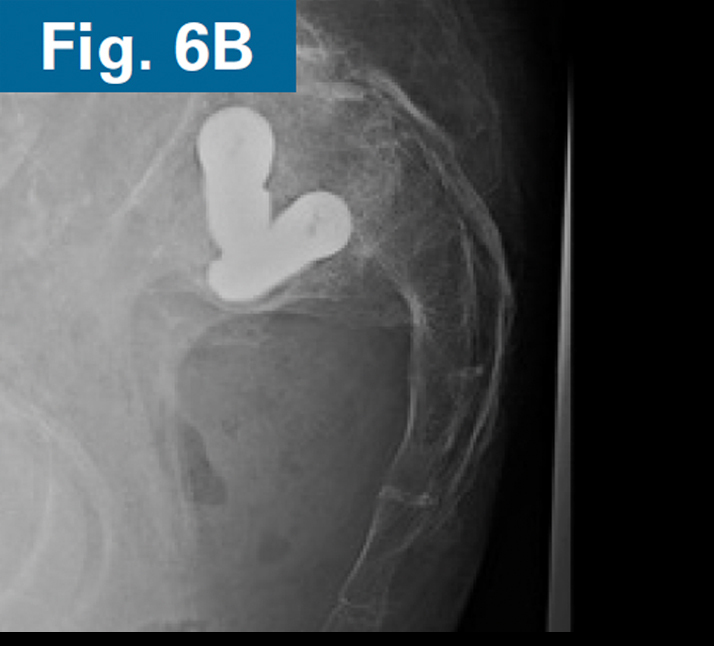

• AP and standing lateral sacral view at 3 months follow-up.

• Callous formation noted on the lateral radiograph (Figs. 6A and 6B).